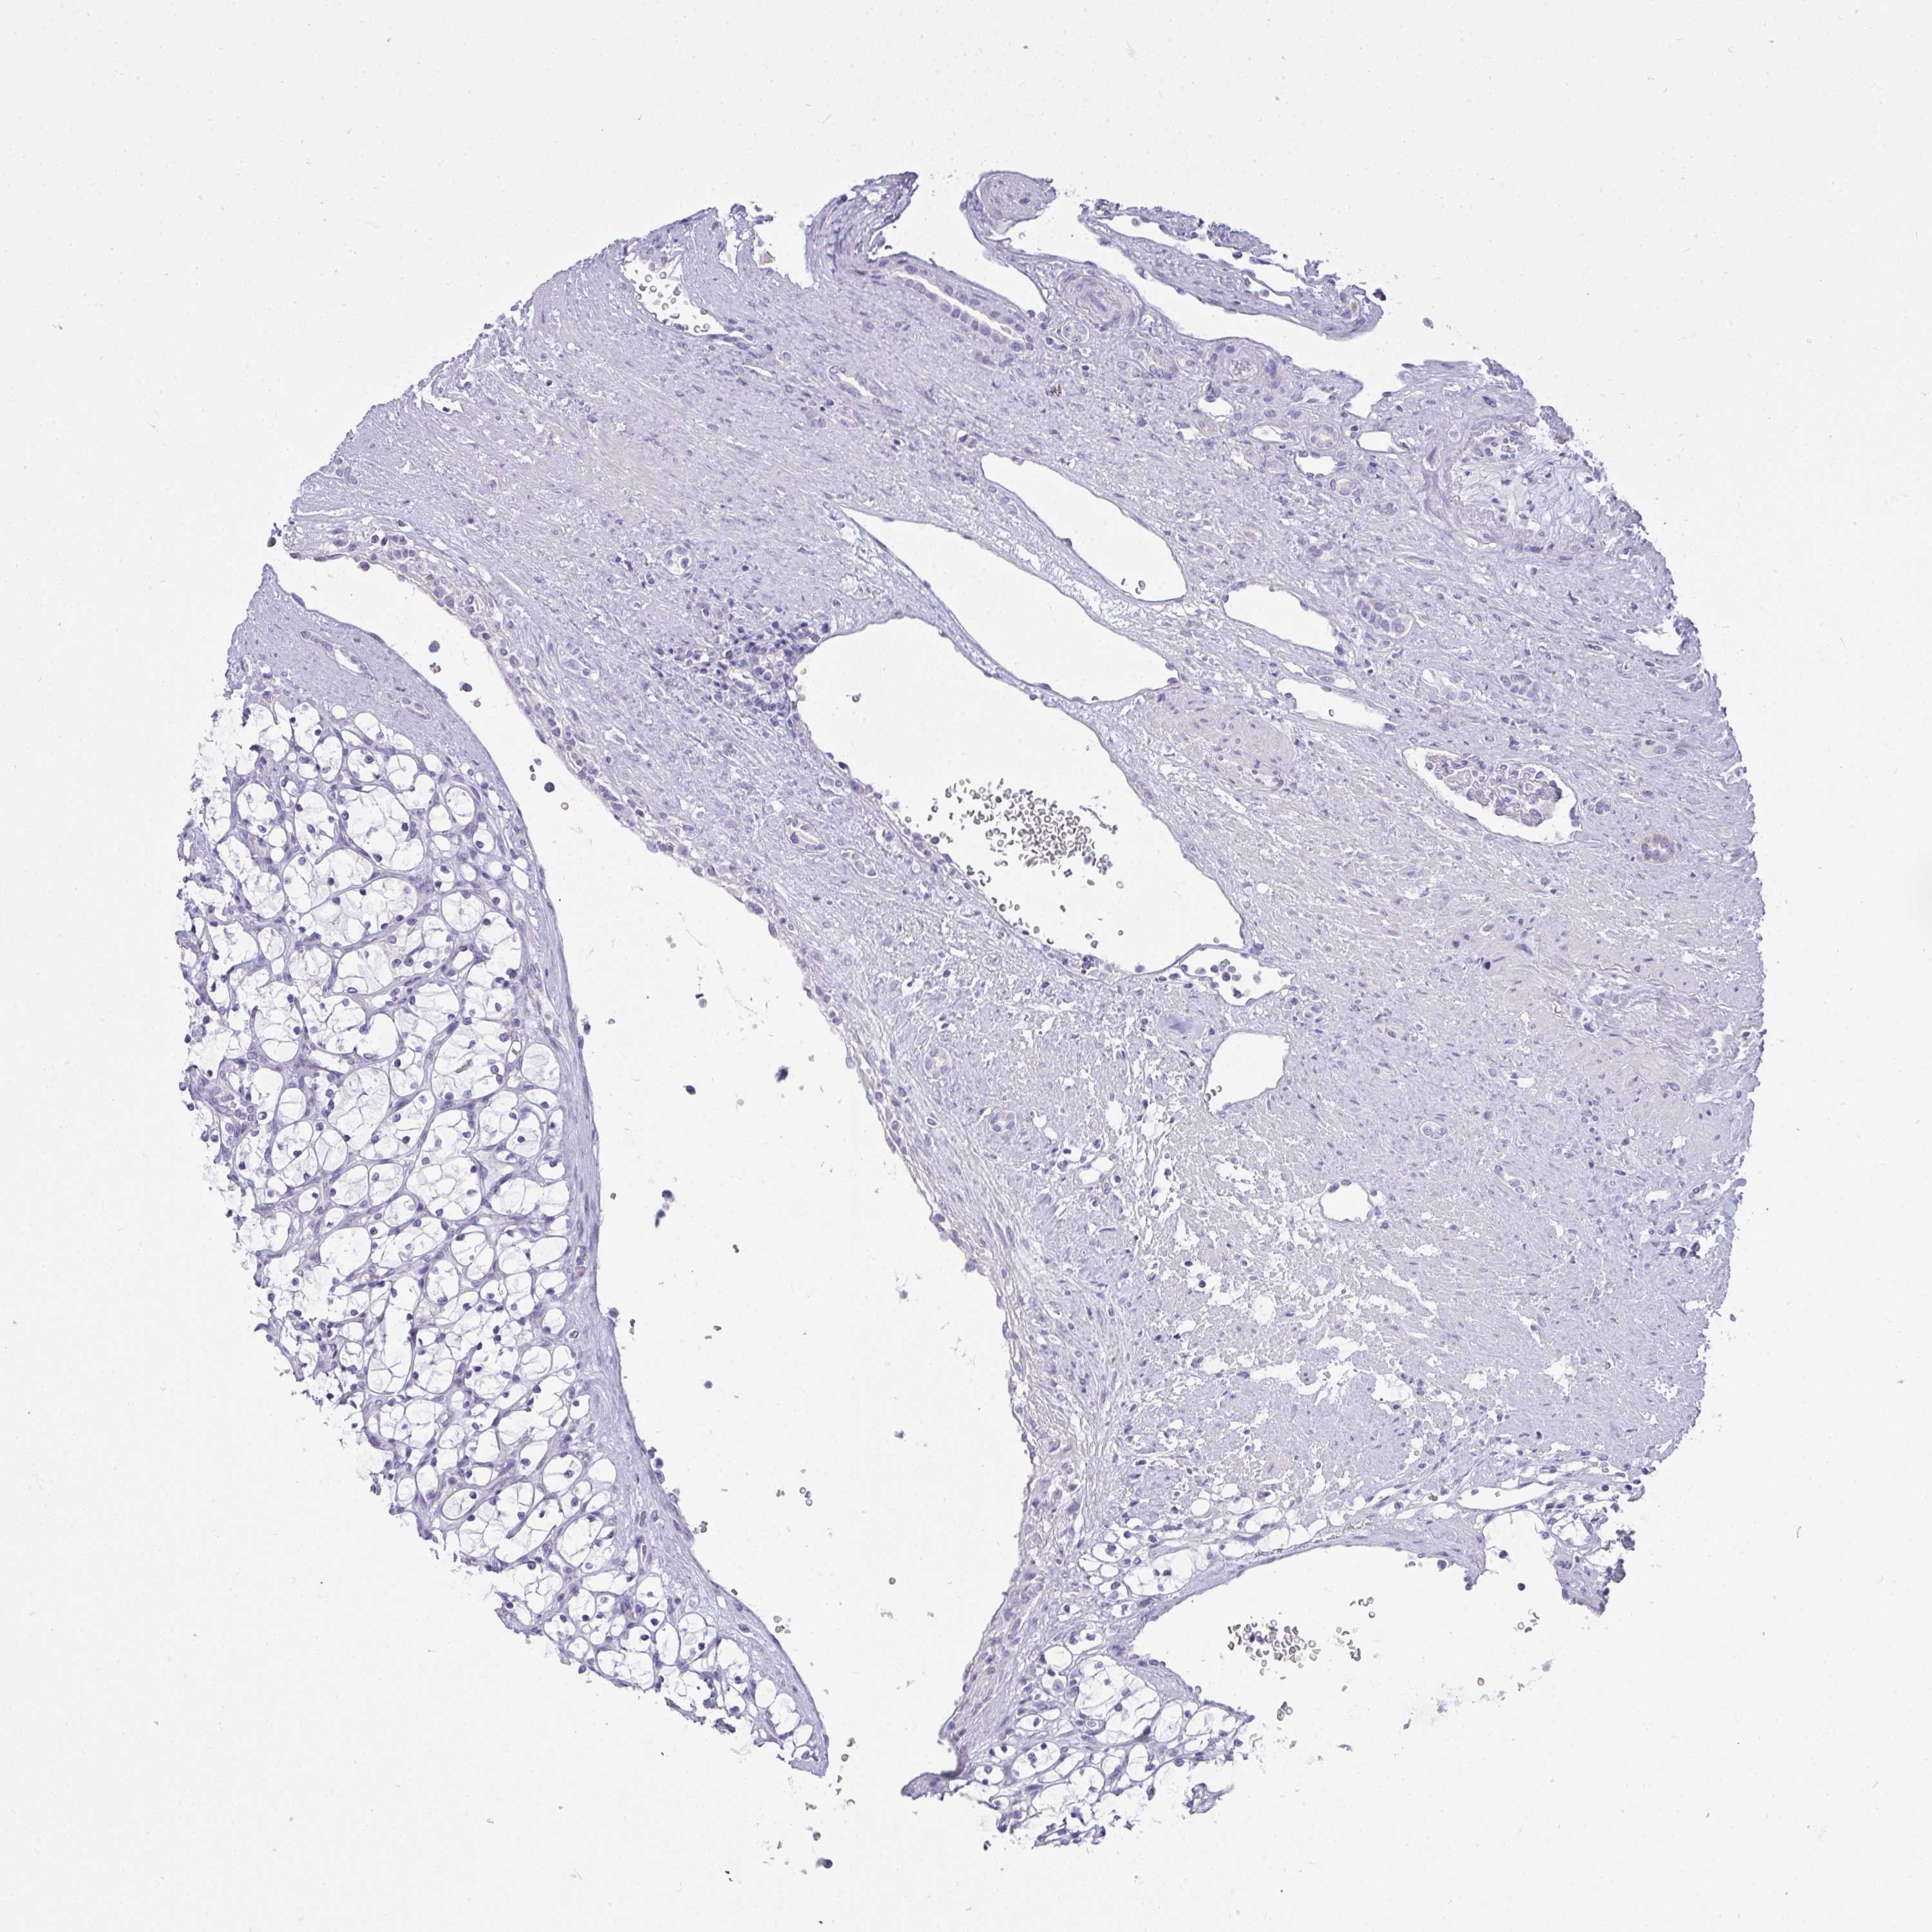

KIDNEY RENAL PAPILLARY CELL CARCINOMA (TCGA) - Interactive survival scatter ploti

The Survival Scatter plot shows the clinical status (i.e. dead or alive) for all individuals in the patient cohort, based on the same data that underlies the corresponding Kaplan-Meier plots. Patients that are alive at last time for follow-up are shown in blue and patients who have died during the study are shown in red.

The x-axis shows the expression levels (FPKM) of the investigated gene in the tumor tissue at the time of diagnosis. The y-axis shows the follow-up time after diagnosis (years). Both axes are complimented with kernel density curves demonstrating the data density over the axes. The top density plot shows the expression levels (FPKM) distribution among dead (red) and alive patients (blue). The right density plot shows the data density of the survived years of dead patients with high and low expression levels respectively, stratified using the cutoff indicated by the vertical dashed line through the Survival Scatter plot. This cutoff is automatically defined based on the FPKM cutoff that minimizes the p-score. The cutoff can be changed by dragging the vertical line or by entering a cutoff value in the square labeled "Current cut-off".

Under the Survival Scatter plot the p-score landscape (black curve; left axis) is shown together with dead median separation (red curve; right axis). Dead median separation is the difference in median mRNA expression between patients who have died with high and low expression, respectively. It is calculated as follows: median FPKM expression of dead patients with high expression - median FPKM expression of dead patients with low expression. This is intended to aid the user in visually exploring custom cutoffs and the associated p-scores and dead median separation.

Individual patient data is displayed and can be filtered by clicking on one or more of the category buttons on the top of the page. Categories describing expression level and patient information include: high, low, alive, dead, female, male and tumor stages. The scale of the x-axis can be toggled between linear and log-scale by clicking on the "x log" button. Mouse-over function shows TCGA ID, patient information and mRNA expression (FPKM) for each patient.

& Survival analysisi

Kaplan-Meier plots summarize results from analysis of correlation between mRNA expression level and patient survival. Patients were divided based on level of expression into one of the two groups "low" (under cut off) or "high" (over cut off). X-axis shows time for survival (years) and y-axis shows the probability of survival, where 1.0 corresponds to 100 percent.

GSDMB is not prognostic in Kidney Renal Papillary Cell Carcinoma (TCGA)

: 1.36